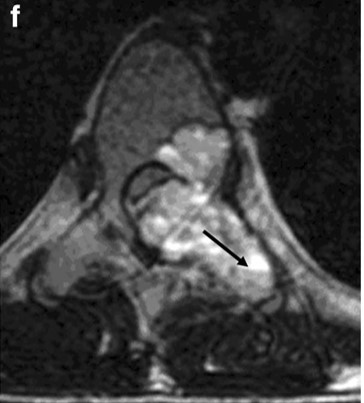

• T2WI

• T1WI

• Gd-T1WI